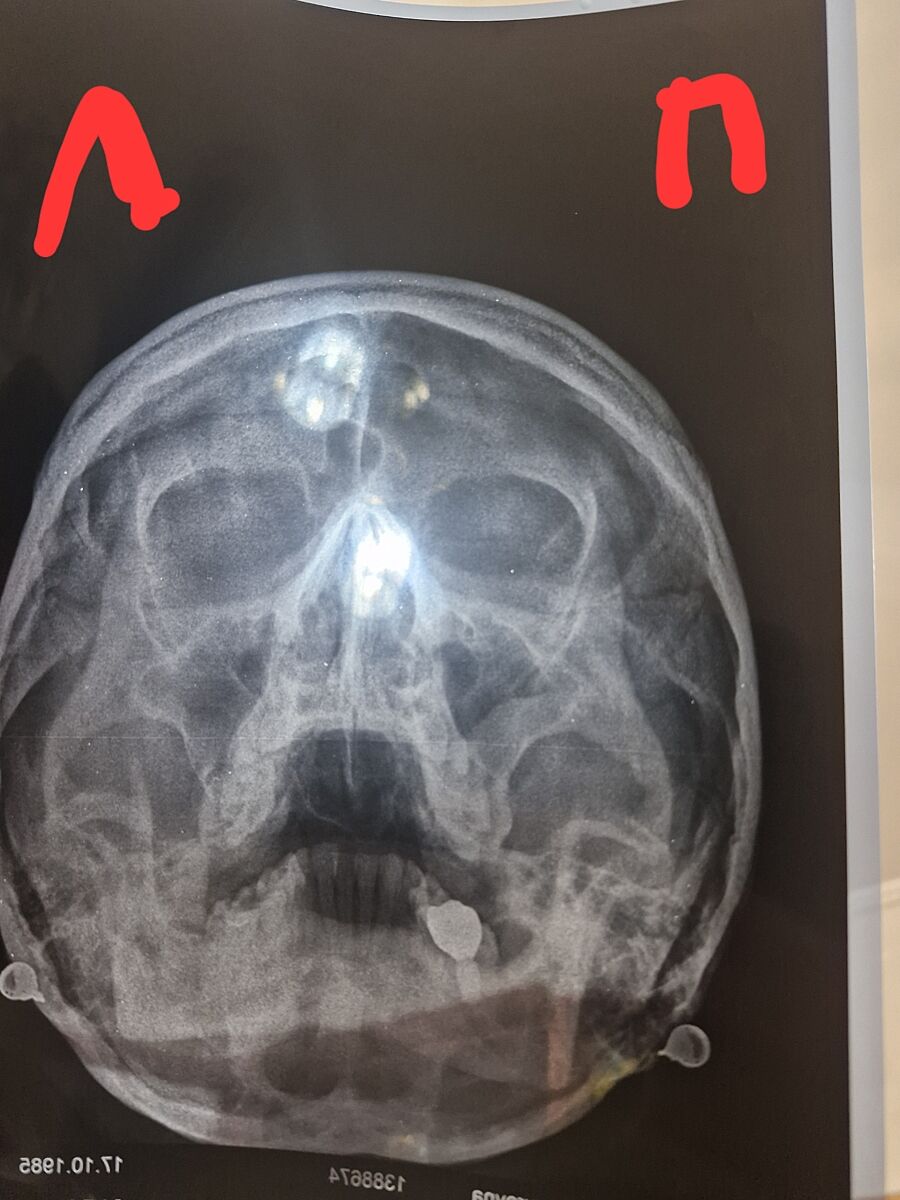

Тут є гайморит?

Врач каже нема гною, але по рентгену гайморит. Мені здається справа оте світле і є гній..хіба ні?

Оця фігня біла, у пазусі))в другій такого нема. Світле в пазухах це гній зазвичай...

Это может быть воспаление или экксудат ( обычная слизь) Что вам выписали?